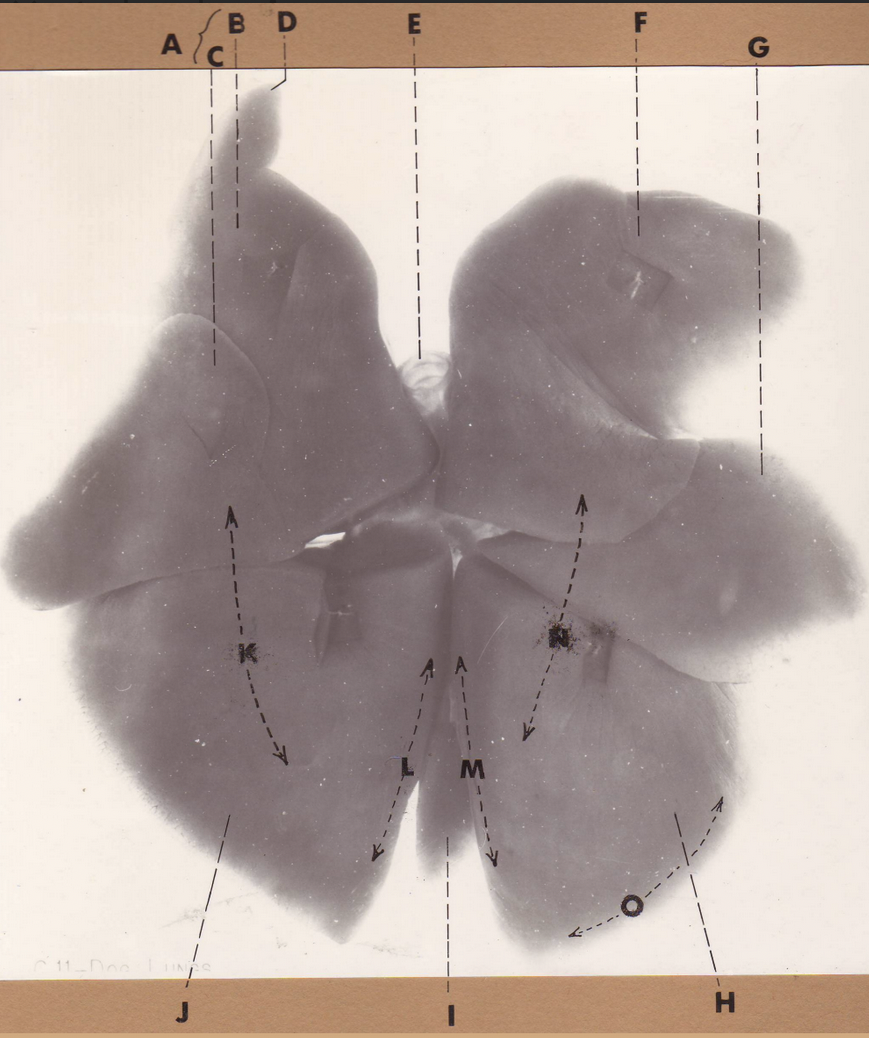

A

(pig lungs, ventral)

middle lobe

B

(pig lungs, ventral)

cardiac notch

C

(pig lungs, ventral)

R cranial lobe

D

(pig lungs, ventral)

tracheal bronchus

E

(pig lungs, ventral)

L cranial lobe, cranial segment

F

(pig lungs, ventral)

cardiac notch

K

(pig lungs, ventral)

trachea

G

(pig lungs, ventral)

L cranial lobe, cranial segment

H

(pig lungs, ventral)

accessory lobe

I

(pig lungs, ventral)

L caudal lobe

J

(pig lungs, ventral)

R caudal lobe

A

(pig lungs, ventral)

middle lobe

B

(pig lungs, ventral)

cardiac notch

C

(pig lungs, ventral)

R cranial lobe

D

(pig lungs, ventral)

tracheal bronchus

E

(pig lungs, ventral)

L cranial lobe, cranial segment

F

(pig lungs, ventral)

cardiac notch

K

(pig lungs, ventral)

trachea

G

(pig lungs, ventral)

L cranial lobe, cranial segment

H

(pig lungs, ventral)

accessory lobe

I

(pig lungs, ventral)

L caudal lobe

J

(pig lungs, ventral)

R caudal lobe